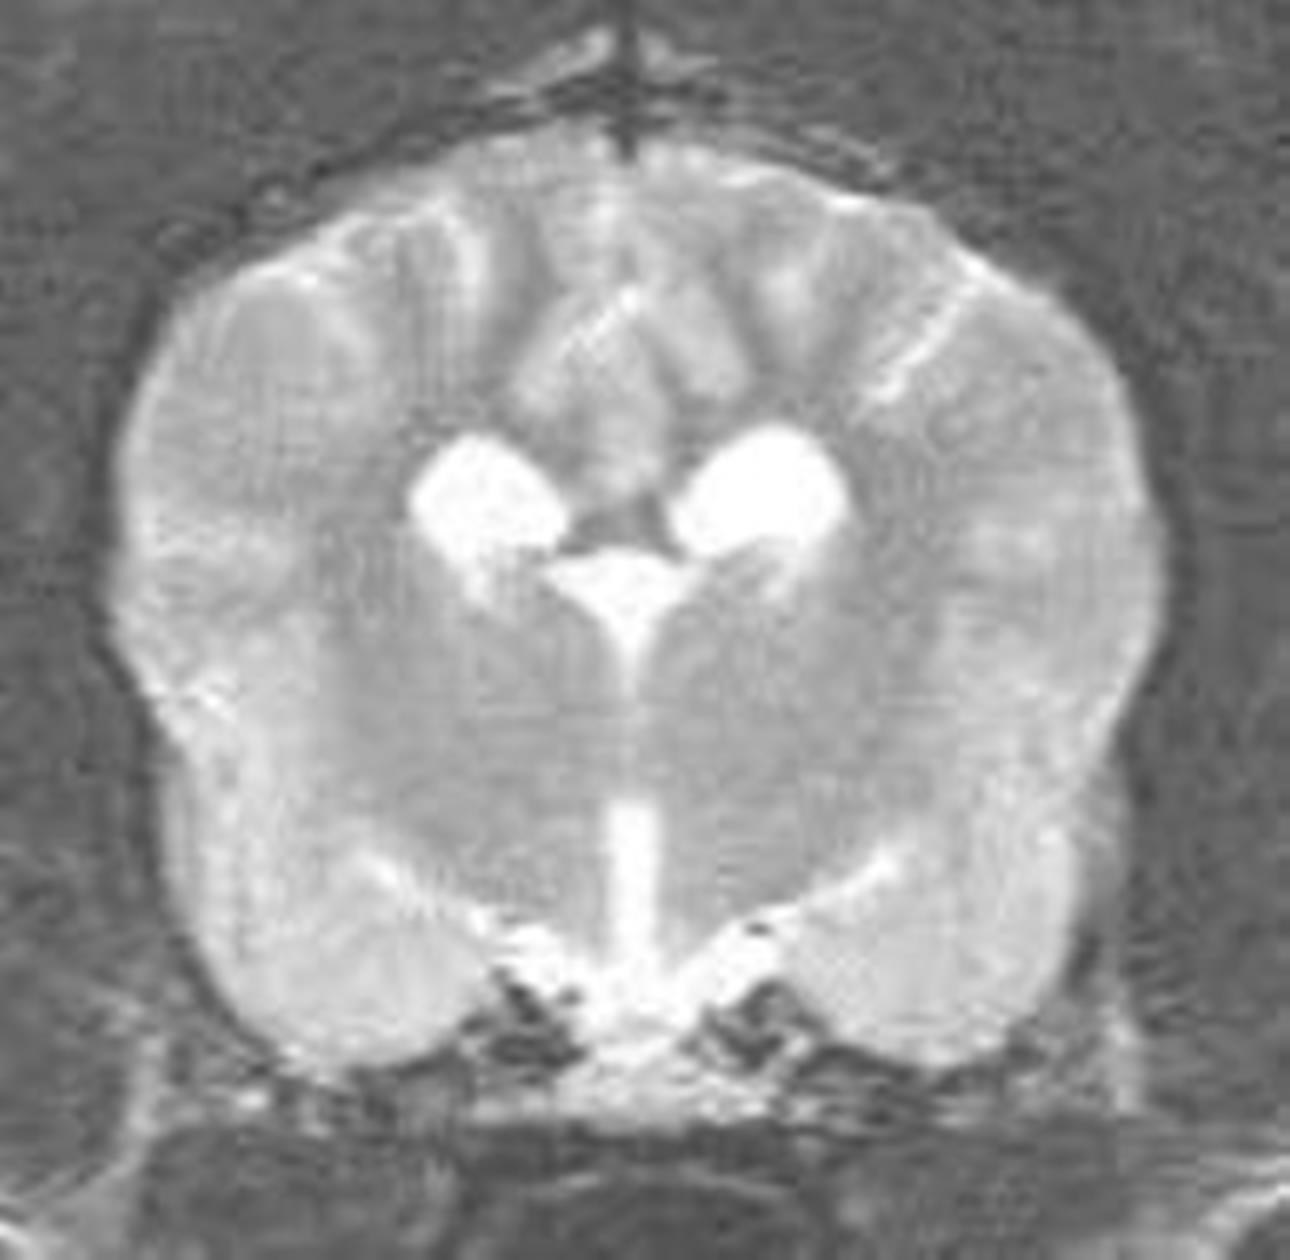

Skip wurde ausführlich körperlich untersucht, besonderes Augenmerk wurde auf die neurologische Untersuchung, vor allem seine Reflexe gelegt (Bild 1 und 2). Diese Untersuchungen verliefen absolut unauffällig. Es bestand kein Verdacht auf eine Funktionsstörung irgendeines Organs, die die Anfälle hätte erklären können. Die Befunde der allgemeinen und neurologischen Untersuchungen wurde durch eine umfangreiche Blut-und Urinuntersuchung ergänzt. Besonders wichtig ist die Überprüfung der Leberfunktion durch die Messung des Blutammoniaks, da eine Leberfunktionsstörung einerseits Ursache epileptischer Anfälle sein kann, andererseits die Medikamente zur Bekämpfung von Krampfanfällen häufig über die Leber verstoffwechselt werden müssen. Bei Skip waren alle Werte absolut normal. Eine weitere Abklärung möglicher Ursachen einer Epilepsie ist jetzt nur noch in Narkose möglich und beinhaltet die Kernspintomographie (MRT) und eine Hirnwasseruntersuchung. Nun besagt eine Studie aus Hannover, dass Hunde wie Skip, die beim ersten Anfall jünger als 6 Jahre waren und bei denen alle Voruntersuchungen bisher unauffällig verliefen, in 10% der Fälle eine krankhafte Veränderung des Gehirns aufweisen. Bei älteren Hunden liegt dieser Anteil mit 25% deutlich höher. Die Besitzer von Skip wollten auch die letzten 10% der Zweifel an einer idiopathischen Epilepsie ausschließen. Daher ließen sie die noch fehlenden Untersuchungen durchführen. Das MRT konnte keine strukturellen Veränderungen im Kopf nachweisen und das Hirnwasser enthielt keine Hinweise auf eine Entzündung des Gehirns. (Bild 3)